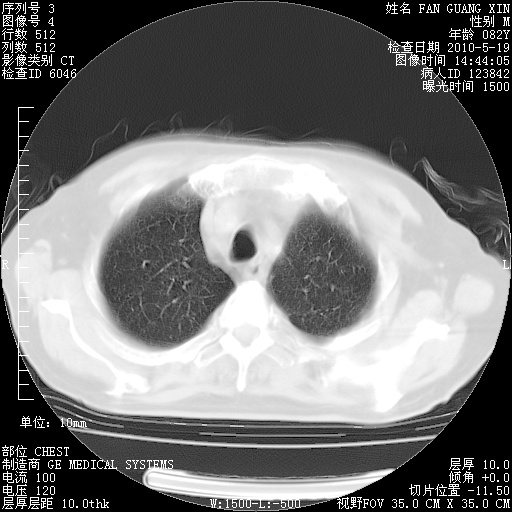

复查肺部CT,明显好转。为什么发热呢?

治疗3周后的肺部CT

治疗3周后的肺部CT纵隔窗